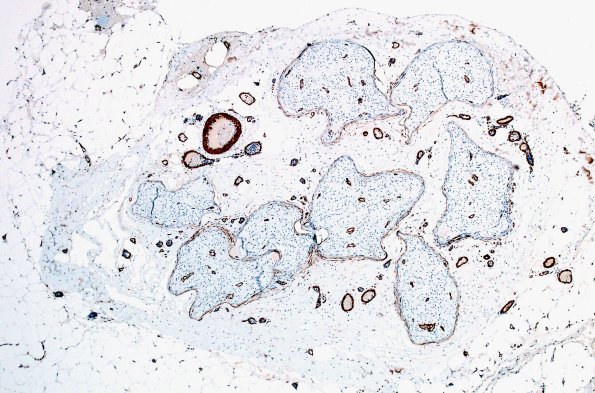

A smooth muscle actin immunostain also demonstrates fascicular shape. (SMA IHC)